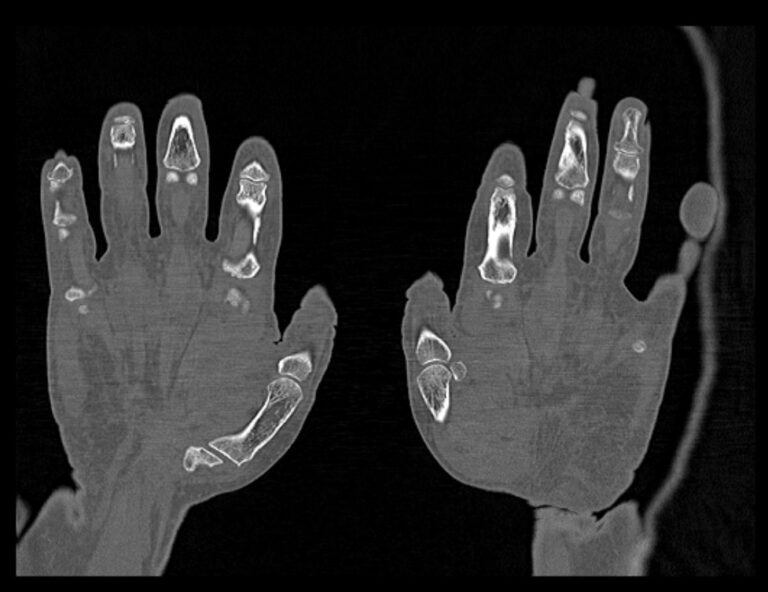

Мультиспиральная компьютерная томография является наиболее точным и информативным методом диагностики травматических повреждений и различных заболеваний костей и суставов пальцев рук. КТ относится к лучевым методам обследования, то есть основан на применении рентгеновского излучения. Быстрота выполнения, неинвазивность (не нужно вмешательство в организм), доступная стоимость делают это исследование незаменимым в травматологии и ортопедии. С помощью КТ проводится диагностика вывихов, ушибов, переломов костей пальцев руки.

При помощи проникающей способности рентгеновских лучей томограф производит послойное сканирование исследуемой области. В результате получаются детальные снимки, а после цифровой обработки данных – подробные трехмерные изображения кисти и пальцев руки.

В наших медицинских центрах КТ пальцев рук выполняется на новейших мультиспиральных компьютерных томографах экспертного уровня TOSHIBA AQUILION. Современное оснащение аппаратов позволяет получать детальные изображения высокого уровня четкости и контрастности, что обеспечивает точность и достоверность диагностики. При этом за счет скоростного мультисрезового сканирования пациент получает уменьшенную дозу рентгеновского облучения.